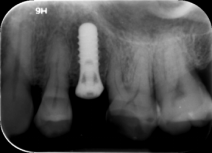

种植牙复查

像拔智齿、补牙、做根管治疗、牙周病、种植牙、牙齿矫正等等都需要拍片。牙片基本属于常规检查。

牙片是治疗牙齿过程中重要的手段之一,在治疗前可以用于发现病变程度;治疗中确定治疗范围和深度;治疗后用于观察疗效。通过牙片,口腔医生可以了解蛀牙范围有多大,牙痛是由牙髓神经发炎、根尖炎症还是牙周炎等引起的,镶牙的条件是否足够,种植牙需要的骨量,发现发育畸形以及某些肿瘤等。另外,牙片还为医患沟通提供了很好的依据。